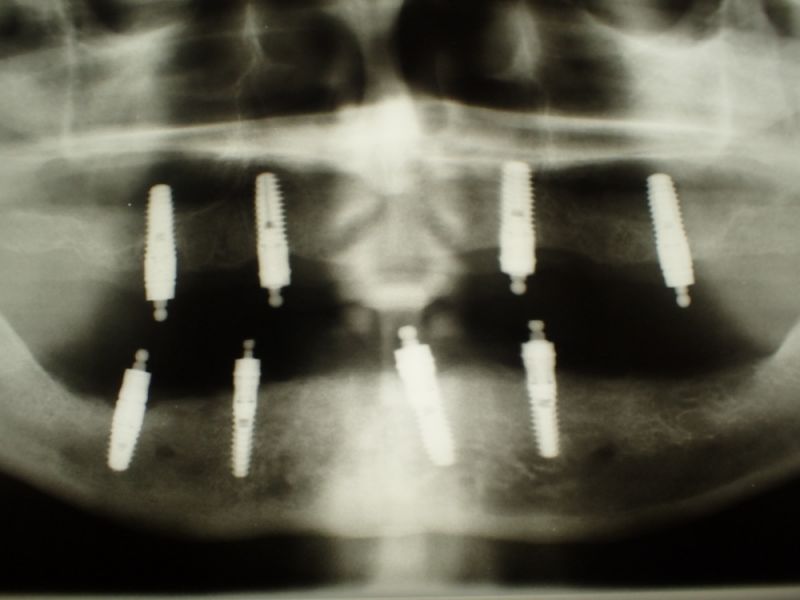

2007 wurde diese implantatgestützte Versorgung erstellt. Die 8 Implantate wurden allesamt hier inseriert und befinden sich bis heute, vollkommen unverändert in Funktion.

Hier eines der großewn Probleme, gerade im Bereich der Implantate, dass Implantathersteller insolvent werden, oder aber bestimmte Ersatzteile einer Produktlinie nicht mehr produziert werden.

Derartige Probleme können dann am Ende dazu führen, dass volkommen intakte Implantate mit erheblichen Knochenverlusten aus dem Kieferknochen herausgefräst, augmentiert und dann neue Implantate inseriert werden müssen.